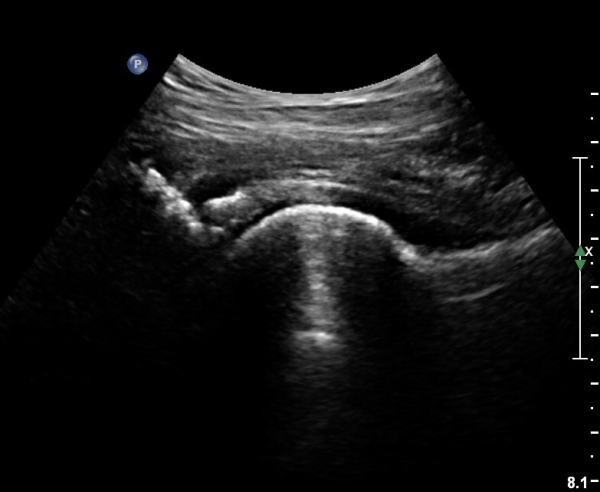

[¾ûµ¢ÀÌ] ¾ûµ¢ÀÌ °üÀý¼ø ÆÄ¿­ÀÇ ÃÊÀ½ÆÄ°Ë»ç(ultrasonography of labrum tear of hip joint)

Sonography of the Acetabular Labrum Visualization of Labral Injuries During Intra-Articular Injections

What is the role of clinical tests and ultrasound in acetabular labral tear diagnostics?

Sonographic evaluation of anterosuperior hip labral tears with magnetic resonance arthrographic and surgical correlation.